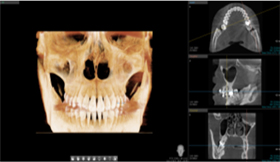

Digital 3D CT

Following a detailed examination of the oral structures including teeth and alveolar bone, 3D CT imaging is used to evaluate key neural pathways and anatomical structures.